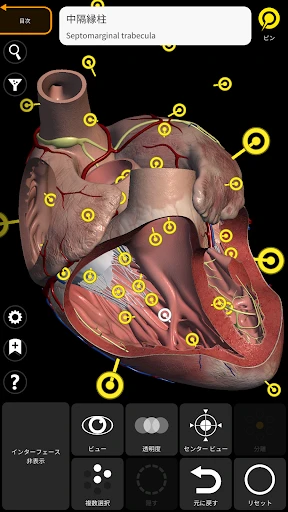

3Dアトラスの驚きの体験

皆さん、3Dで人体を探検したことはありますか?このアプリを使うと、まるで本物の標本を手に取っているかのように、人体の構造を詳細に観察できます。何よりも嬉しいのは、非常にリアルなグラフィックスです。3Dモデルはとても精密で、筋肉や骨、内臓の位置関係が一目瞭然です。

この「解剖学 - 3Dアトラス」、ただのビジュアルツールにとどまりません。かなり多くの情報が詰まっています。例えば、各部位の詳細な説明や、医学用語の解説も充実しているので、学習にはもってこいです。特に、試験勉強中の学生さんには非常に役立つことでしょう。

私のお気に入りの機能の一つは、特定の部位を選択すると、その部位に関する詳細な情報が表示されることです。これにより、単なるビジュアルだけでなく、知識を深めることができるのです。